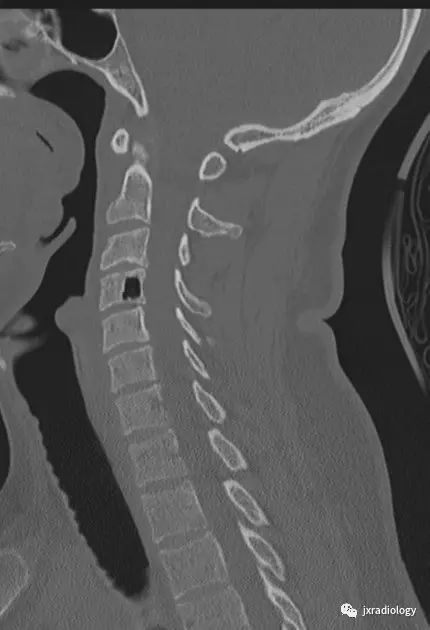

颈腰椎CT片,看到椎骨里的气体密度影,你会考虑什么?相信很多同行朋友会有此类困惑。今天带大家一起学习下该病。

影像资料:

CT:被认为是最好的诊断方法,CT值约-800~-1000HU,椎体及椎间隙内可见气体可以看到相连续的层面,有时会向硬膜外扩张。MRI:气体在T1及T2均为低信号,易和硬化性病变混淆,CT有助于诊断。随访发现一些病灶会增大,但不需要特别治疗。